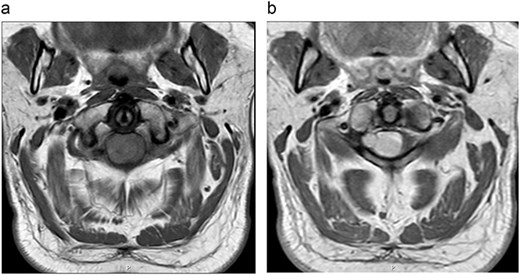

MRI cervical spine (Fig. 1) demonstrated an extramedullary intradural lesion at C1/2 within the right aspect of the canal distorting and compressing the cord to the left with associated cord signal changes. The lesion is isointense on T1- and T2-weighted images and measures ~1.7 × 2.0 × 2.1 cm. Following contrast (Fig. 2), there is homogenous enhancement of the lesion. Computed tomography of thorax, abdomen, and pelvis showed no evidence of primary lesions or skeletal deposits.

(a) Pre-operative axial MRI cervical spine T1-weighted image without contrast (across the C1 level). (b) Pre-operative axial MRI cervical spine T1-weighted image with contrast (across the C1 level).